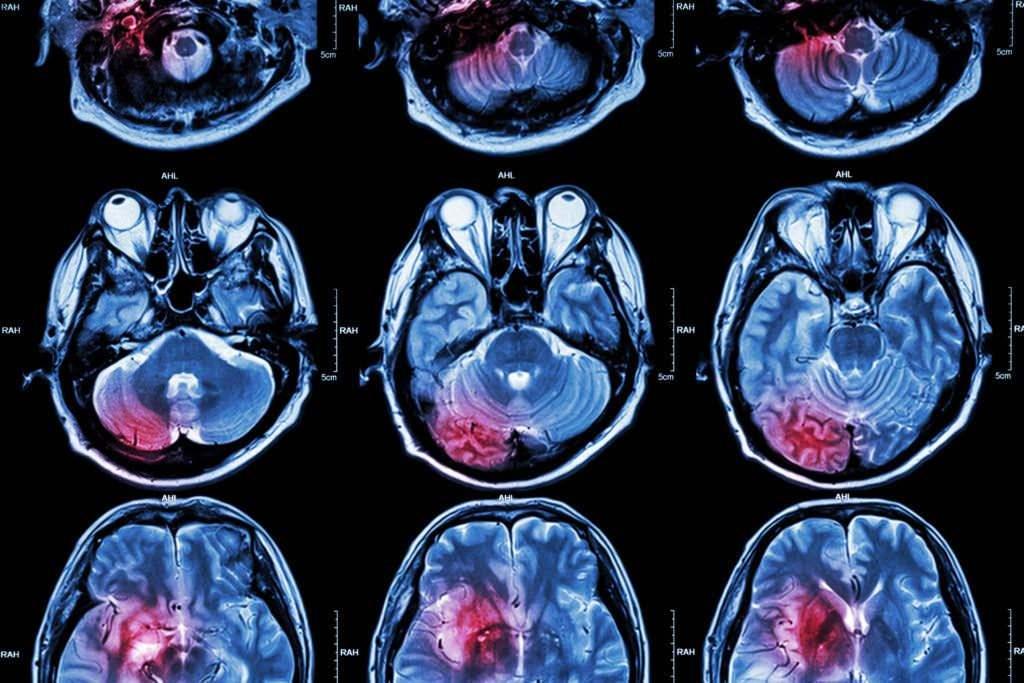

Henüz 14 yaşında olduğu için baş ağrılarının ergenliğin bir modülü olduğunu sanan Jade Jackson, “Teşhisim konulmadan evvel hayat hoştu. Birinci belirtileri gösterdiğimde 14 yaşındaydım ve baş ağrılarının hormonal olduğunu düşünüyorduk. Bir gün okuldan konuta gelip kendimi kanepeye attığımda daha önemli olduğunu fark ettim. Başımda anında dayanılmaz bir ağrı hissettim ve gidip kustum. O vakit bir şeylerin döndüğünü anladık. Oradan çabucak MRI çektirmeye gittik” halinde konuştu.

“Başlangıçta korkmuş ve endişelenmiştim ve ‘neden ben?’ niyeti aklımdan geçmeye devam etti.” diyen Jackson, “Gerçekten ‘Aman Yaradanım, beyin kanseri oldum’ hissi yerleşti. Korkmuş ve telaşlı olsam da Rab’ın ve ailemin her adımda benimle olacağını biliyordum, bu da bana huzur verdi.” ifadelerini kullandı.

Teşhisten sonra 10 yıldan fazla mühlet yaşayanlar arasında %47’lik bir oranda yer alan Jade Jackson; “Geçtiğimiz 11 yıl boyunca çok sayıda tedavi gördüm. Altı hafta boyunca tam beyin ve omurga radyasyonu ve oral kemoterapiyle başladı. Ondan sonra klinik bir denemeyle birlikte birden fazla farklı kemoterapi gördüm. Şu anda çok sayıda uzun vadeli yan tesirim var ve bu hayatımı sahiden etkiliyor. Nöropati muhtemelen en büyüğü. Hepsi beni günlük işlerimi yapmaya sonlandırıyor. Birtakım günler yalnızca olağan günlük yürüyüş bile benim için sıkıntı ve çok acı verici oluyor. Her günü dolu dolu yaşayabildiğim için kendimi şanslı hissediyorum” diyerek hayatta kalabildiğini ancak beyninde oluşan hudut hasarı nedeniyle uyumakta ve yürümekte zorluklar çektiğini ifade etti.